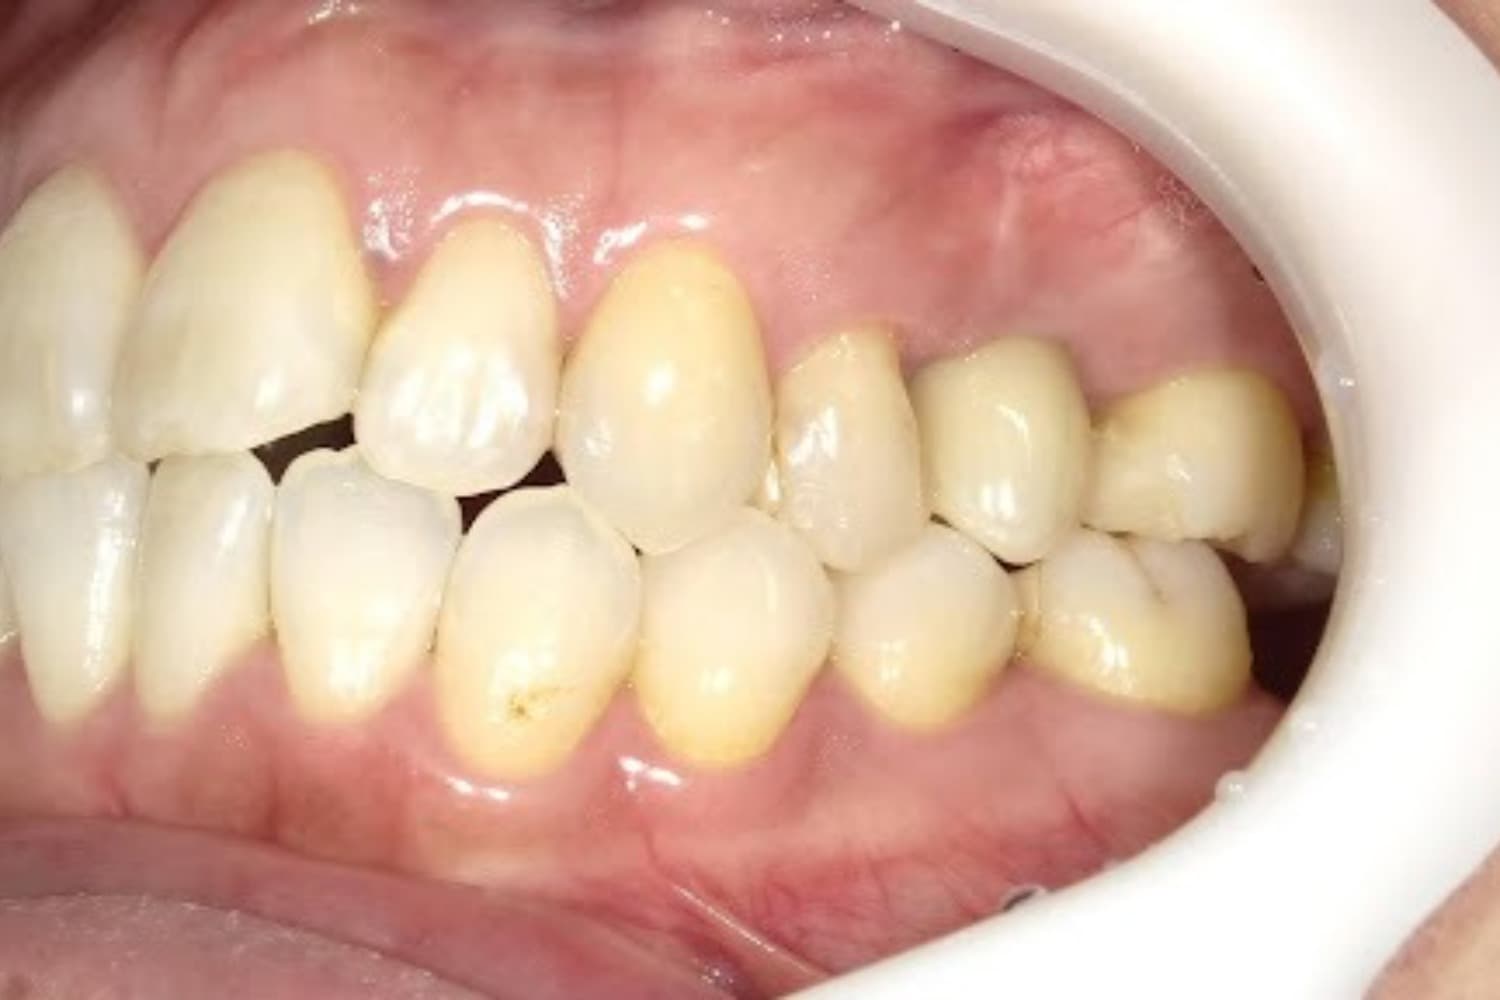

左上の歯のインプラント治療(40代女性)

Before

After

抜歯をおこない上顎洞内及び歯抜した周囲組織の回復を試みたあと、グラフトレスサイナスリフト・人口骨補填をともなうインプラント治療

年齢

50代

性別

女性

主訴

左上の歯が歯根破折を起こしていた。何もしていなくとも痛みを感じる。

治療期間

2ヵ月半

治療回数

6回

費用

368,500円(税込) 費用の内訳: 【インプラント基本料】330000円(税込み) 基本料金に以下を含む ・フィックスチャー及び手術費用 ・投薬費用、 ・レントゲン費用 ・インプラント上部費用(アバットメントおよびジルコニアクラウンの費用用) 【オプション費用】 ・グラフトレスサイナスリフト費用+人工骨費用 38500円(税込み)

副作用・リスク

・手術後に痛み・腫れ・出血・合併症等を引き起こす恐れがあります。 ・噛む感覚がご自身の歯と異なることがあります。 ・見た目がご自身の歯と異なる場合があります。 ・手術後もメインテナンスを続けないと、インプラントが抜け落ちてしまう恐れがあります。